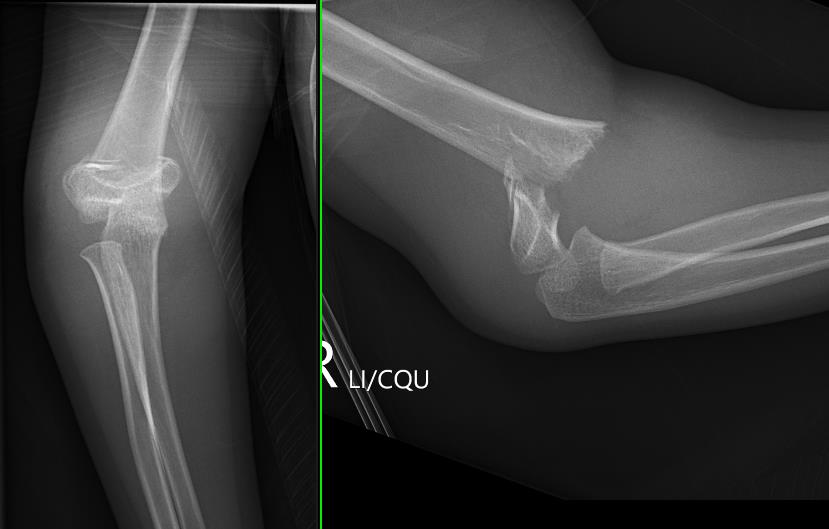

Lateral Xray

Position for good lateral

- thumb vertical

- hand above elbow

Anterior angulation

- shaft - condylar axis

- normally 40o

Lines

Anterior humeral line (AHL)

- should pass through middle of capitellum

Radio-capitellar line

- pass through capitellum

Teardrop

- shadow above the capitellum

- anterior dense line: posterior margin of the coronoid fossa

- posterior dense line: anterior margin of the olecranon fossa

- inferior portion: ossification center of the capitellum